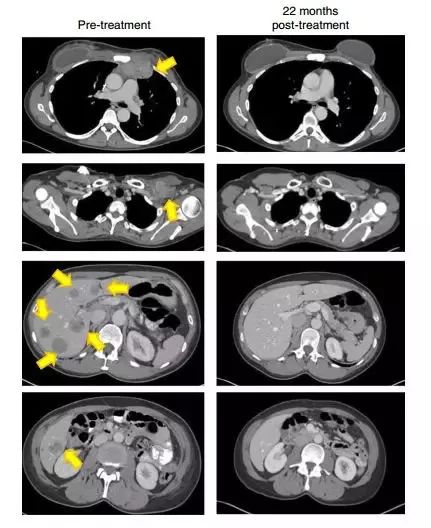

晚期乳腺癌接受治疗22个月后,这名患者的肿瘤(黄色箭头)消失得无影无踪

(图片来源:《Nature Medicine》)

一名患有转移性鳞状细胞癌并接受了多种联合化疗方案,包括顺铂,长春新碱和博来霉素,然后用吉西他滨加顺铂联合放疗。随后发现转移,包括主动脉旁,双侧肺门,颅下和髂骨部位(图1A和1C)。治疗后,她在所有疾病部位都完全消退(图1A和1C)。

另一患者患有转移性腺癌。她的原发性肿瘤对化放疗无效。随后转移到更多的腹膜后淋巴结和肝脏表面,在TIL治疗前,她在腹膜后,腹壁,旁系,肝旁和盆腔部位有肿瘤进展(图1B和1d)。在治疗后,出现完全的临床缓解(图1B和1d)。